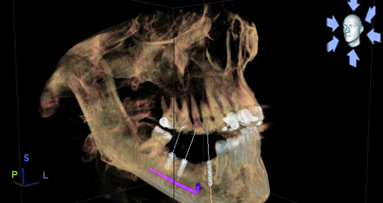

The use of interactive treatment planning software adds advanced software tools to help remove scatter, improve the diagnostic capabilities, while creating three dimensional reconstructed volumes that can be seen in all planes of view. The ability to navigate and ‘slice through’ 3-D volumes, known as ‘clipping’, provides unprecedented visualisation of the maxillo- mandibular structures. A maxillary 3-D volume ‘clipped’ through the right canine (marked in red) is seen in Figs. 4a and b. The 3-D reconstructed volume helps to further define the maxillary alveolar anatomy, tooth, and root position within the bone. An advanced software feature allows for manipulation of the grayscale density of the scan data (thresholding). This tool known as ‘segmentation’ can be used to reduce scatter from metal artifacts, such as crowns or fillings, and to separate one object from another. Through software segmentation, the maxillary right canine can be virtually extracted from the alveolus, illustrating the socket anatomy, the thin facial cortical plate (yellow arrows), and the palatal bone thickness (green arrow) (Fig. 5). The software allows the images to be enlarged for closer inspection (Fig. 6). Note the areas of good density and where the density is poor within the alveolus, superior to the root socket.

The capability to virtually remove a tooth and root from the bone can aid clinicians in making educated decisions regarding immediate extraction-to-implant placement, immediate-to-transitional restoration, and an appreciation of the potential ‘gap distance’, which may be present after implant placement. A simulated implant of the appropriate diameter and length can be positioned within the virtual socket to gain initial stabilisation as related to the desired restorative outcome (Fig. 7). The thin facial cortical bone can be clearly seen (yellow arrow), as can the thicker palatal bone (green arrow). The facial ‘gap’ between the implant and the facial cortical plate can be fully appreciated, and decisions made whether or not to fill the gap with bone (red arrows).